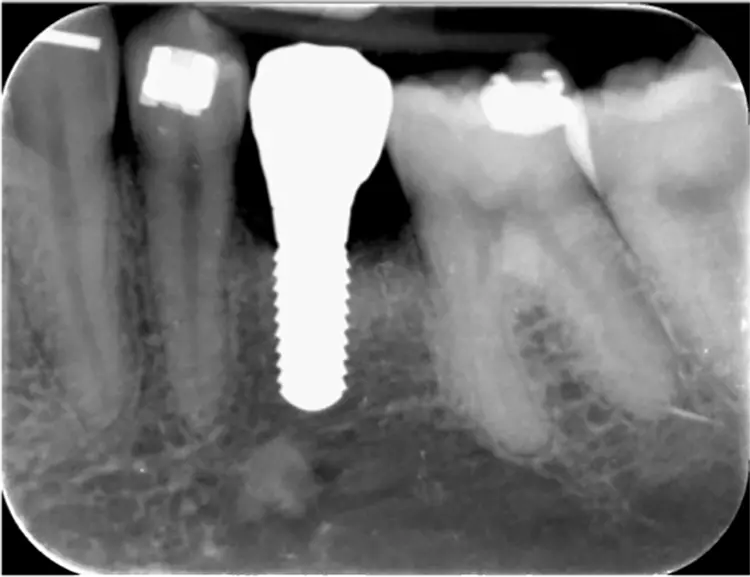

Mittlerweile ist ein Spätverlust aufgrund einer Implantatlockerung nach 9,5 Jahren aufgetreten. Eine Ursache für diesen Verlust ist leider nicht zu ermitteln, da das Implantat im Ausland entfernt wurde. Der Knochenverlust im Zeitraum zwischen Insertion und prothetischer Versorgung betrug im Mittel 0,7 mm (Abb. 4).

Das periimplantäre Knochenniveau blieb, wie oben beschrieben, nach dem initialen Remodelling stabil (vergl. Abb. 4). Überraschend fand sich nach 5 Jahren in beiden Zentren röntgenologisch ein identisches periimplantäres Knochenniveau, und das, obwohl die Implantate in Zürich im Mittel 0,6 mm tiefer gesetzt wurden als in Freiburg [39] (Abb. 8). Ebenso ist die Streuung der Werte in Freiburg und Zürich nach 5 Jahren gleich, die Verteilungskurven liegen jetzt praktisch übereinander.

Der Mittelwert von 1,8 mm entspricht ungefähr dem Literaturwert für die mittlere biologische Breite an Implantaten unter der Annahme, dass das bindegewebige Attachment und das Saumepithel jeweils eine Ausdehnung von etwa 1 mm haben [26] und der Sulkusboden in Höhe der Implantatschulter liegt. Etwas weniger als 40% der Knochenniveaus lagen im Bereich des glatten transmukosalen Bereichs, etwa 20% in der Rille am Übergang vom glatten transmukosalen zum rauen intraossären Bereich und gut 40% im rauen intraossären Bereich (Abb. 9).